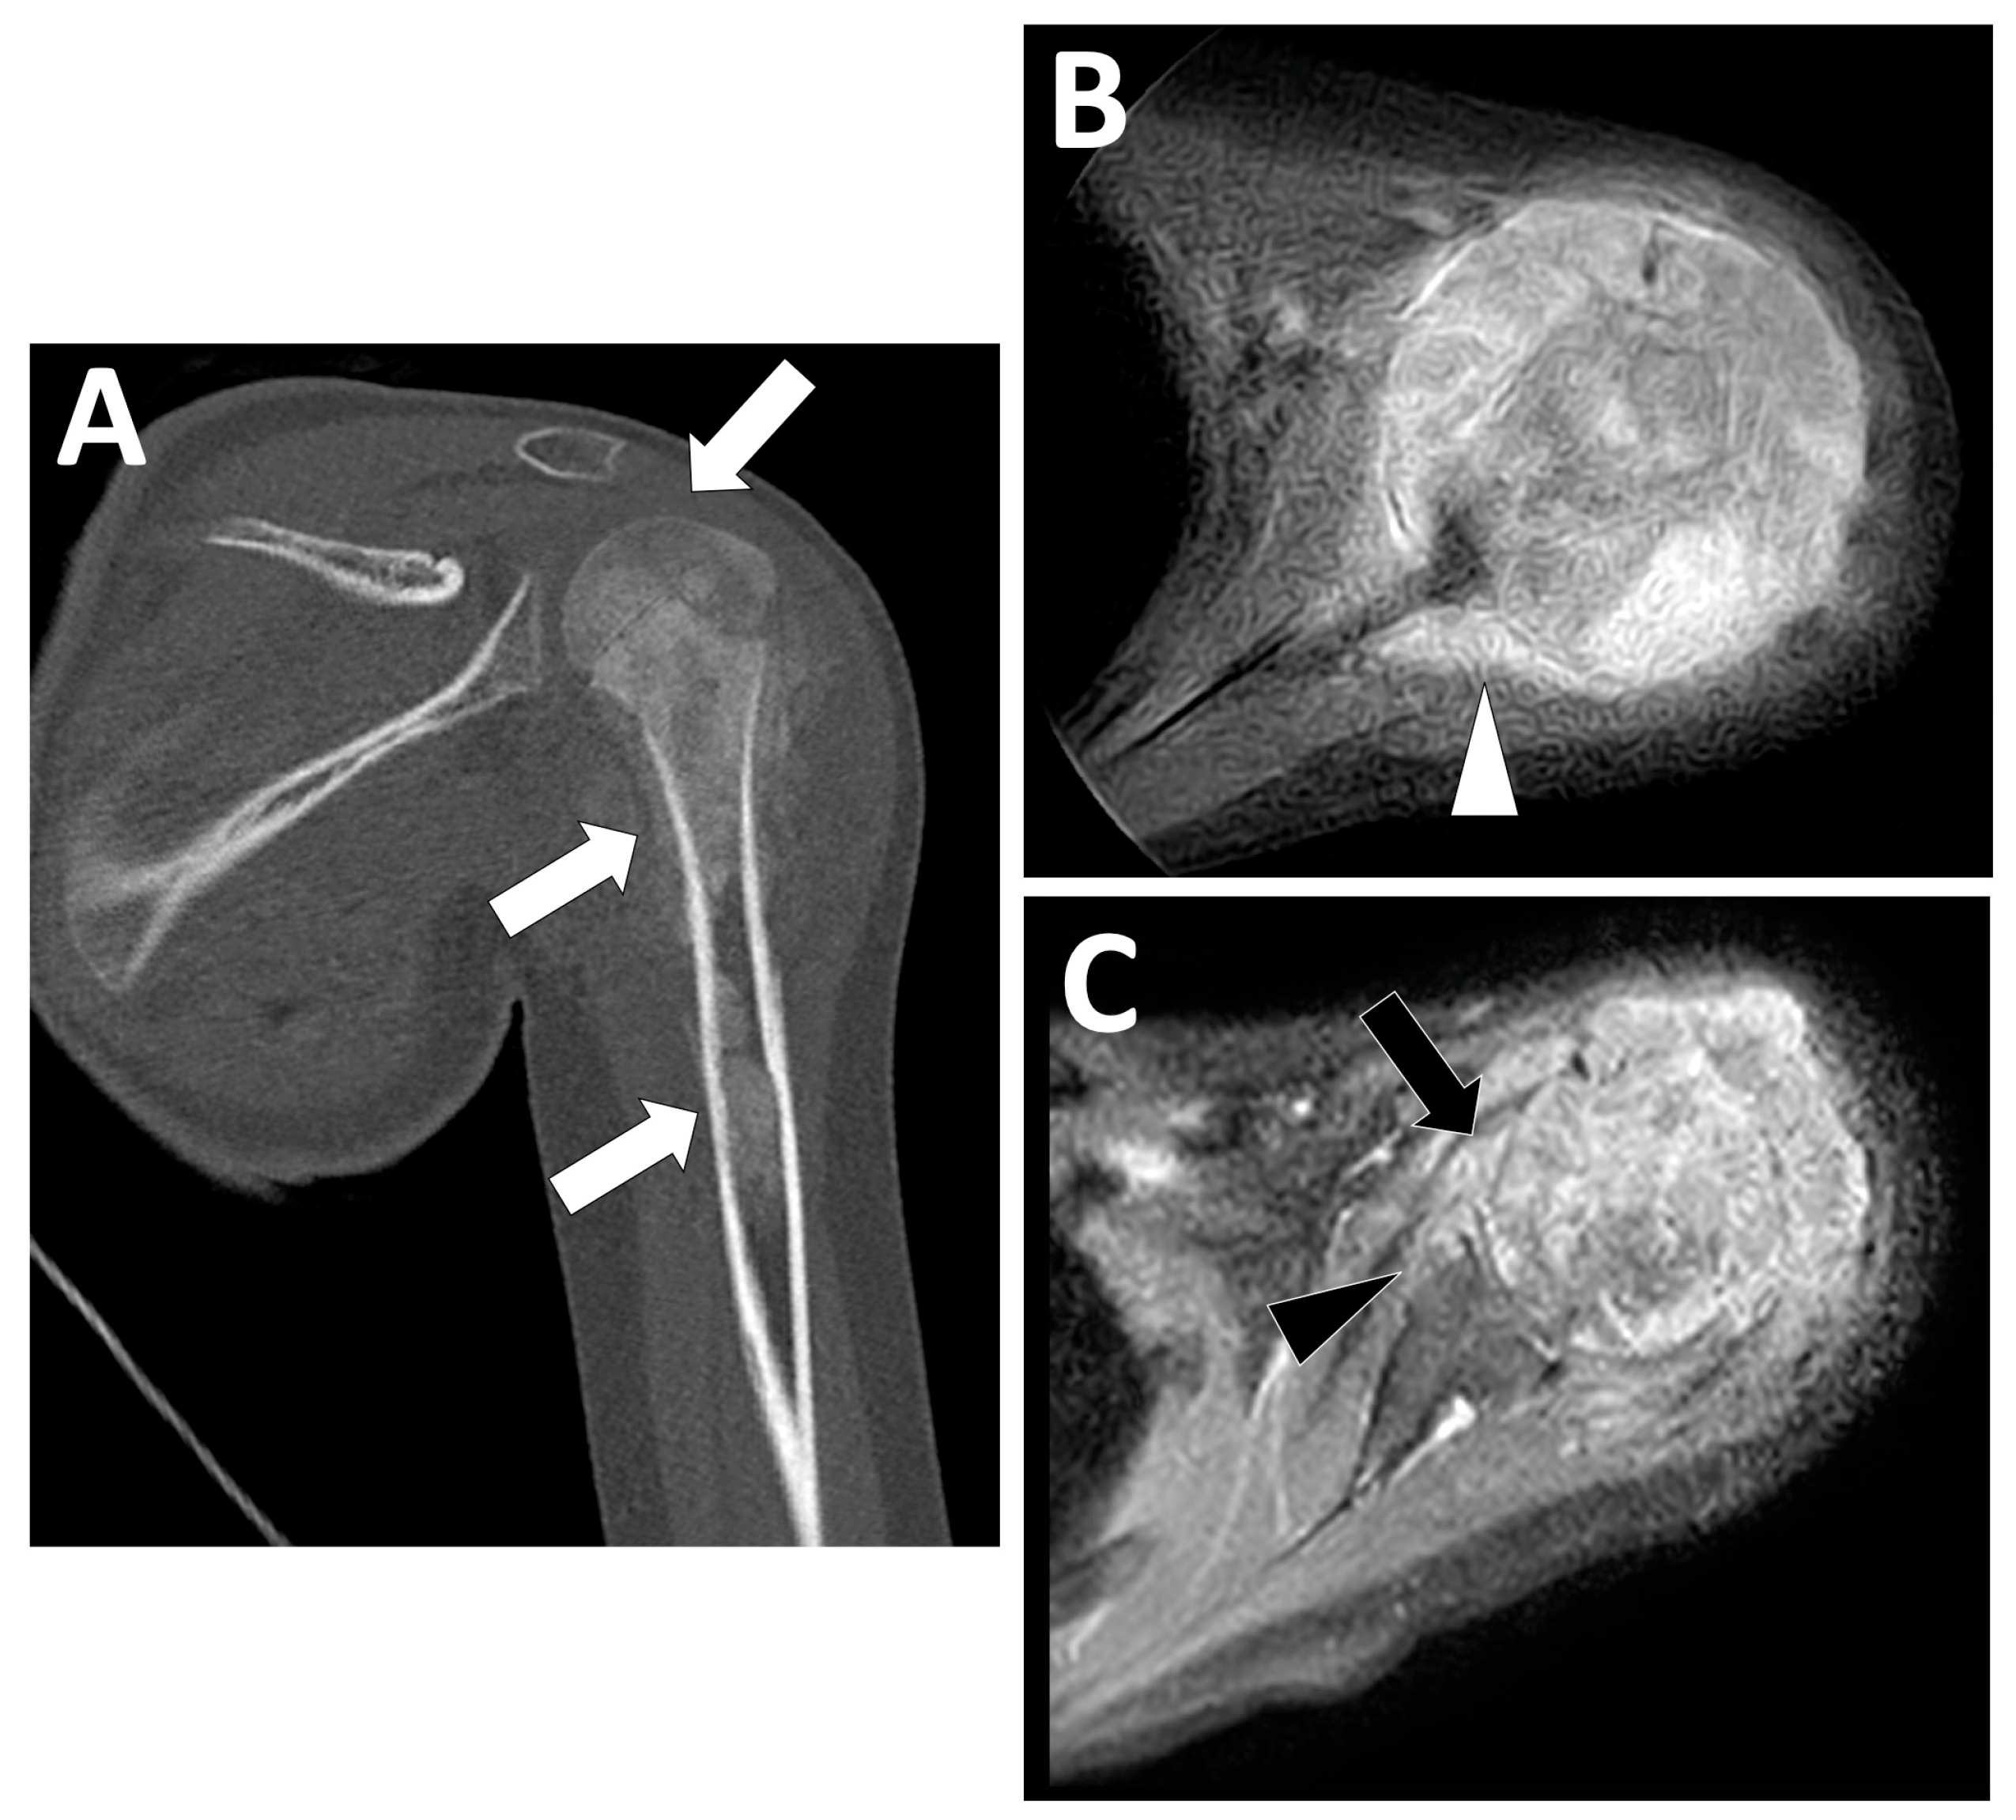

2.3. Radiological Findings on CT

2.4. Radiological Findings on MRI